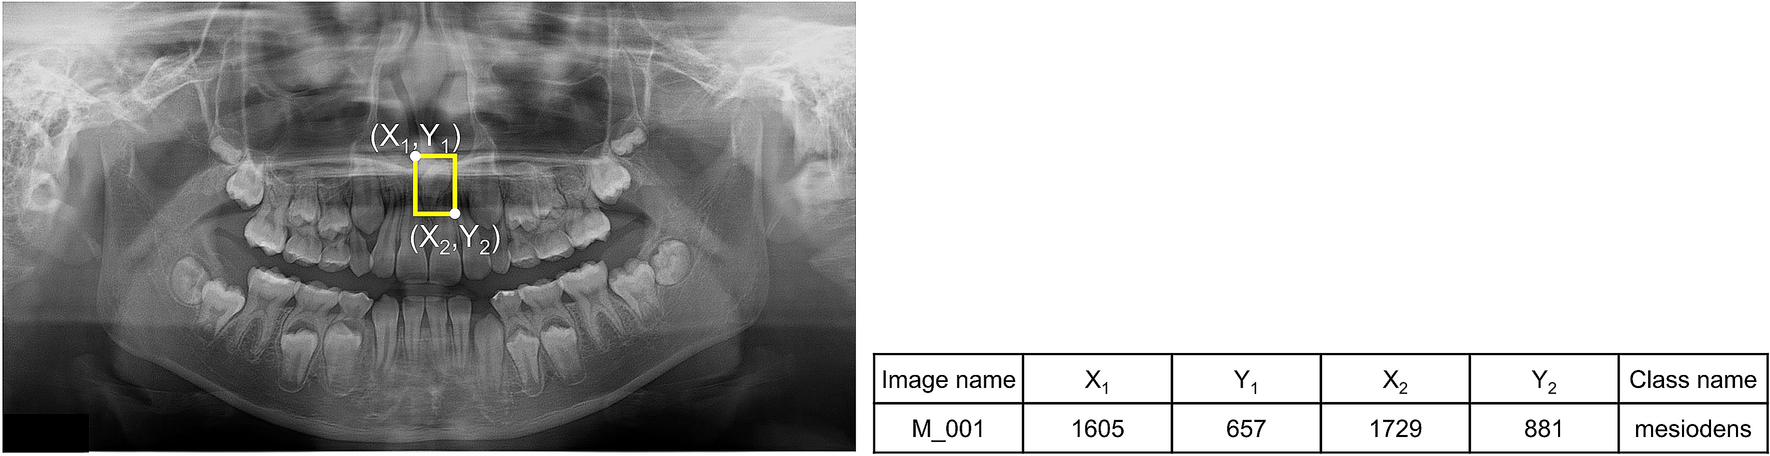

Figure 1

From: Automatic detection of mesiodens on panoramic radiographs using artificial intelligence

The oral radiologist annotated the mesiodens with a yellow rectangular box. The coordinate information of the upper left (X1, Y1) and the lower right (X2, Y2) was determined, and the class name was extracted as “mesiodens.”